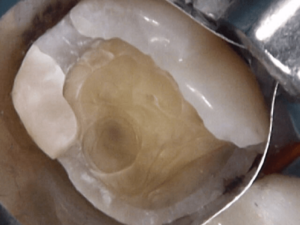

Before and After Treatments

Gordon Street Dental Success Stories in Guelph

Many Patients have allowed us to show what we’ve done for them. Please feel free to look at what we’ve done for them, as well as envision what we can do for you.

Image Grid Title